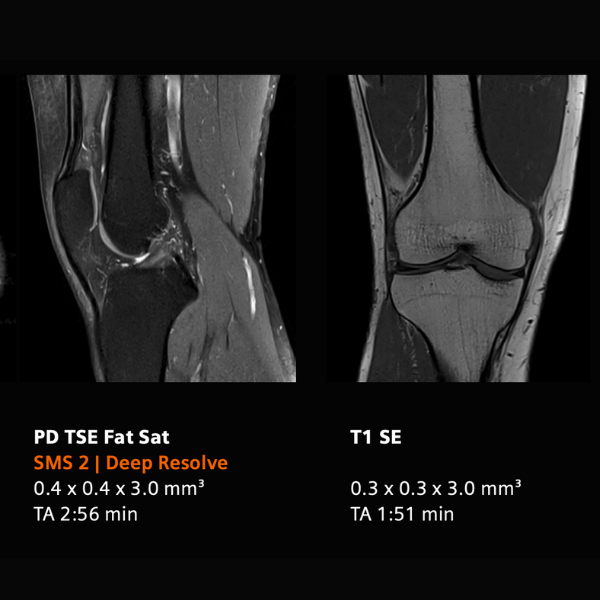

Basado en la innovadora tecnología High-V MRI (0.55T), el MAGNETOM Free.Star combina digitalización, técnicas de adquisición eficientes y reconstrucción con deep learning, proporcionando diagnósticos confiables tanto en estudios de rutina como en nuevas aplicaciones clínicas. Su diseño helium-free, sellado de por vida, elimina la necesidad de recargas y reduce significativamente los costos operativos y de mantenimiento.